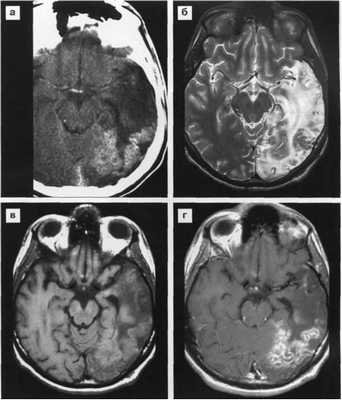

Герпетическая инфекция

![Поражение головного мозга при ВИЧ инфекции]()

КТ картина

- Участки сниженной плотности в височных долях иногда с захватом лобных или затылочных долей.

- Контрастирование маловыражено

- Кровоизлияния визуализируются редко.

- Масс-эффект.

- Распространение процесса по сильвиевым щелям к островку.

МРТ картина

- Ранние проявления отека в лобных и височных долях

- (гиперинтенсивные на Т2 гипоинтенсивные на Т1 зоны)

- Разнообразные признаки масс-эффекта.

- Деструктивные изменения

- Очаги подострого кровоизлияния - гиперинтенсивные по Т1.

- Локализованная или генерализованная атрофия мозга

- Контрастирование по извилинам мозга